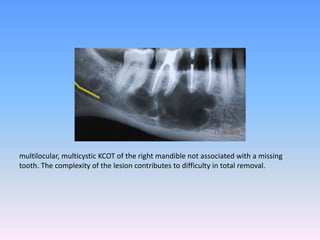

multilocular, multicystic KCOT of the right mandible not associated with a missing

tooth. The complexity of the lesion contributes to difficulty in total removal.